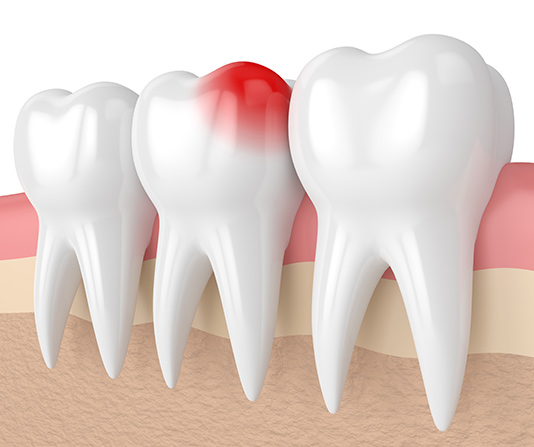

When you have severe tooth pain, it can be a real dental emergency—and Nu Dentistry is here to help you through them all, including teeth extraction. While it may sound scary, our friendly, gentle dentists make sure you’re always relaxed in our office. There are 2 main types of tooth removal procedures: Simple extraction. A simple extraction is used to remove teeth that are visible. Once local anesthetic has properly numbed the area, your dentist will use a tool called an elevator to loosen your tooth and forceps to fully remove it from your gum. Surgical extraction. A surgical extraction is instead performed on teeth that are not visible, like fully submerged teeth or teeth that have broken off below the gum-line. Our on-site oral surgeon will make an incision and extract your tooth directly from your gums. Since this method is more intensive, the surgeon will most likely give you a mix of local anesthetic and sedation, including oral or IV sedation. This ensures both your body and mind are relaxed and comfortable throughout your treatment. After your treatment, we’ll prepare you with aftercare instructions to ensure that your mouth stays healthy and heals quickly without any complications. Within a week or two of your procedure, new bone and gum tissue will fill the gap your tooth left behind. At Nu Dentistry, we understand that you can’t always plan when you have a toothache or when your molars are coming in. That’s why if you need emergency tooth extraction, we’re on-call and ready for you. We do our best to ensure you’re in our patient suites within minutes of your arrival. If you need to call our on-site staff to schedule an immediate appointment, call us now at +18329164144.